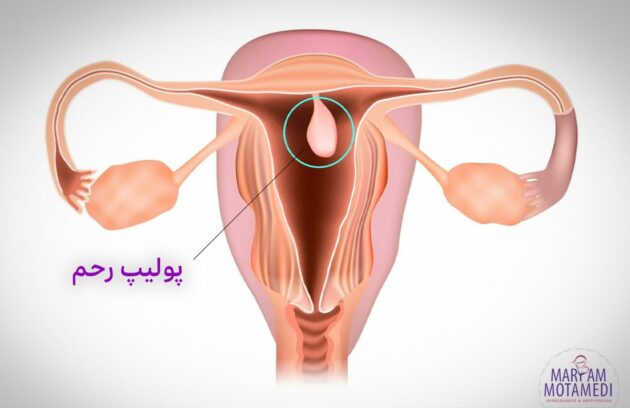

در بعضی از موارد، ممکن است برای بعضی از بانوان و رحمشان مشکلاتی به وجود بیاید. رحم می تواند با…